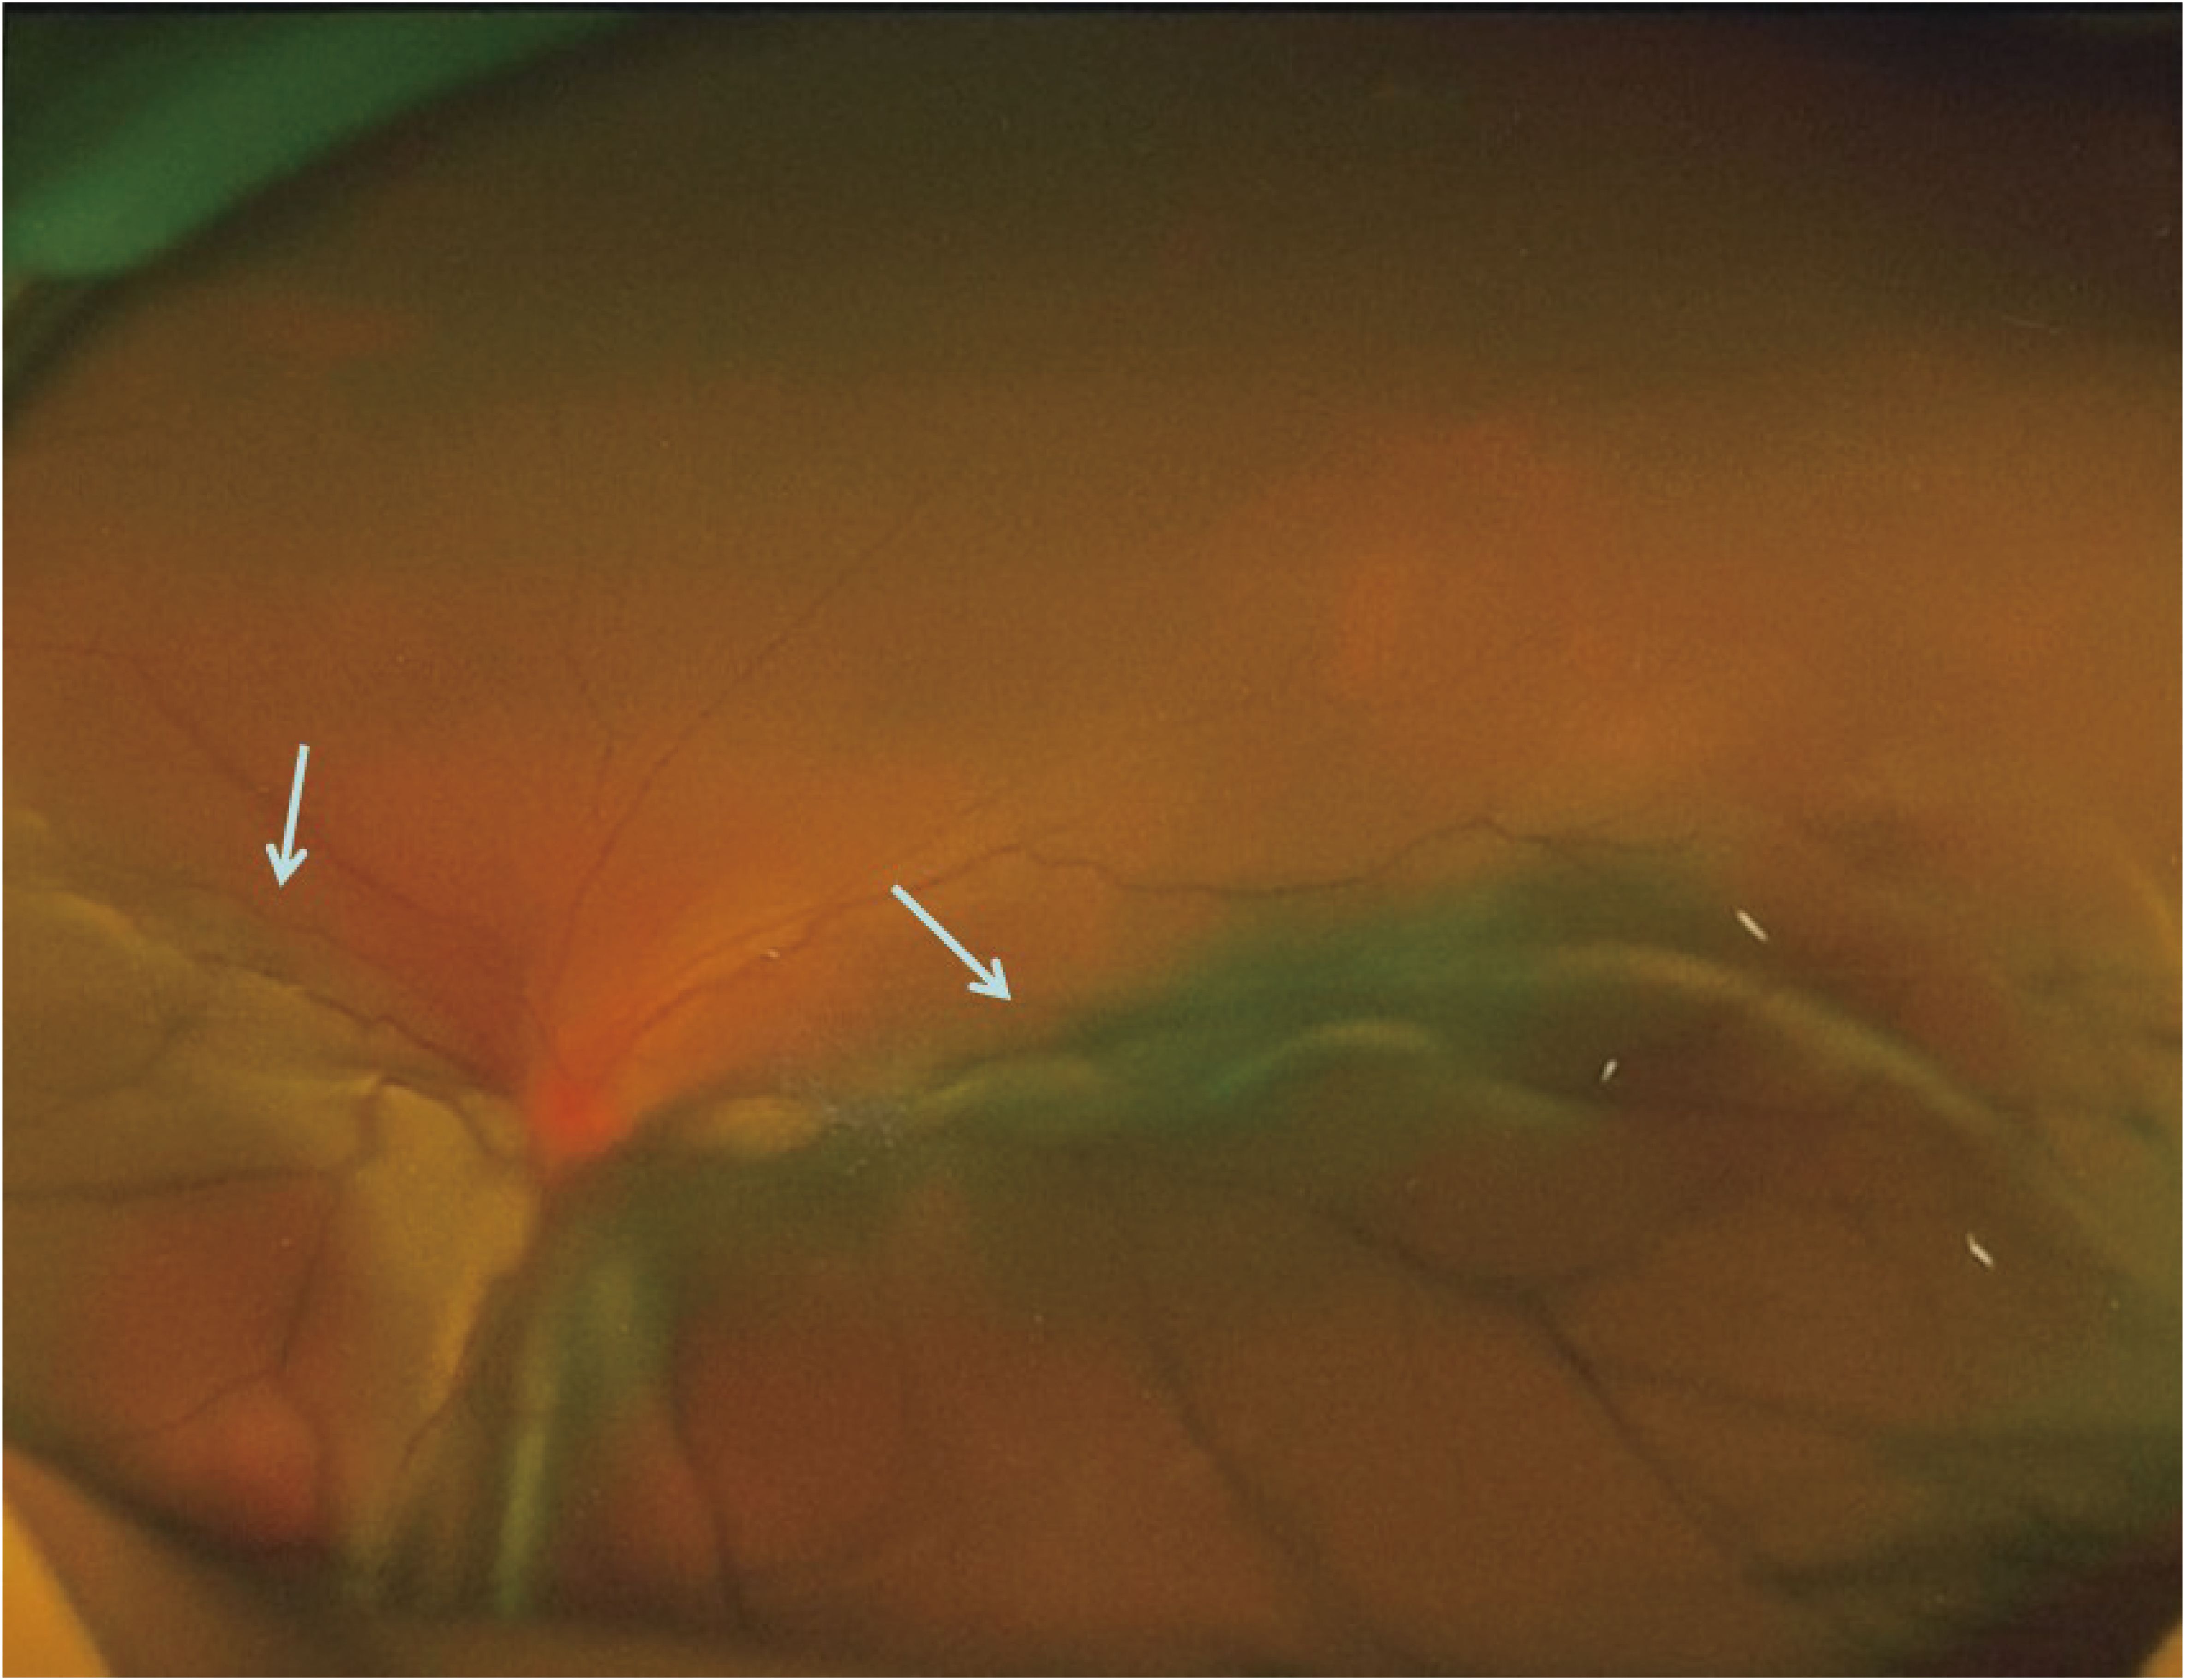

Background: Isolated ocular metastasis from esophagogastric junction (EGJ) cancer is extremely rare, and no standardized therapeutic approach has been established to date. Reporting such cases may help clarify optimal management strategies for uncommon metastatic patterns. Case presentation: We describe a 44-year-old male who developed isolated ocular oligometastasis ten months after radical EGJ cancer resection. Comprehensive evaluation confirmed left-eye involvement. Following multidisciplinary team (MDT) discussion, a combined treatment plan was implemented, starting with systemic therapy consisting of docetaxel, tegafur–gimeracil–oteracil (S-1), and tislelizumab. After achieving disease stabilization, the patient underwent left-eye enucleation with ocular prosthesis implantation, followed by adjuvant radiotherapy and maintenance S-1 chemotherapy. At a 55-month follow-up, he remains disease-free with an excellent performance status (PS 0). Conclusion: This case highlights that integrated multimodal therapy—including systemic and local interventions—can result in long-term survival for patients with isolated ocular metastasis from EGJ cancer. MDT-based, individualized treatment planning is essential for optimizing outcomes in rare metastatic scenarios and may inform future precision oncology approaches.